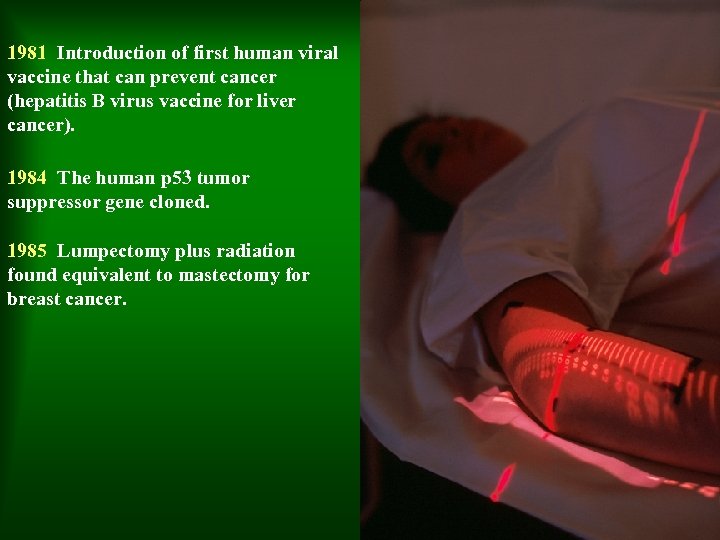

1981 Introduction of first human viral vaccine that can prevent cancer (hepatitis B virus vaccine for liver cancer). 1984 The human p 53 tumor suppressor gene cloned. 1985 Lumpectomy plus radiation found equivalent to mastectomy for breast cancer.